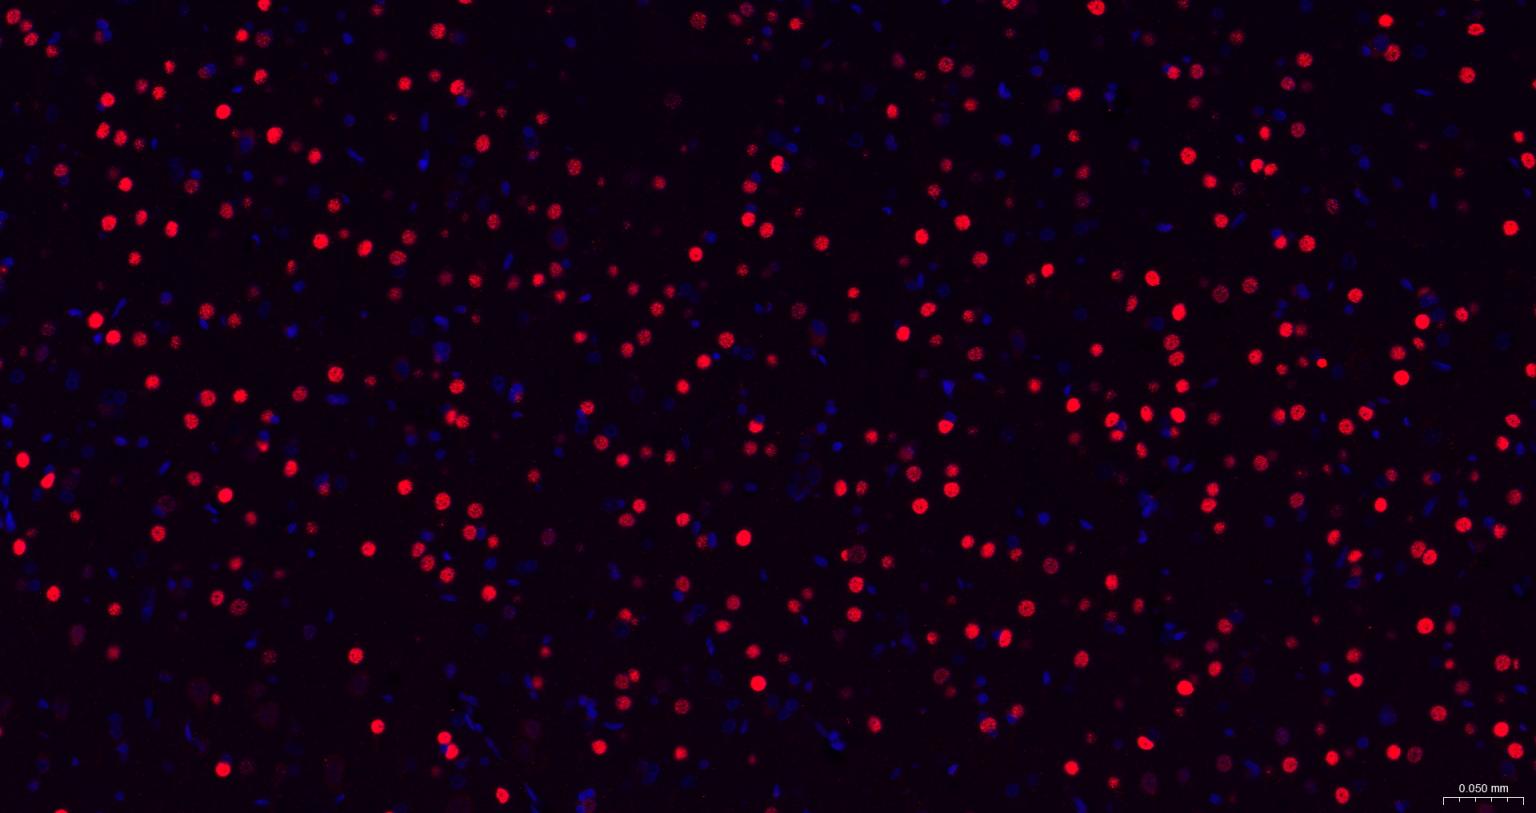

Paraformaldehyde-fixed, paraffin embedded Human Cerebrum; Antigen retrieval by boiling in sodium citrate buffer (pH6.0) for 15 min; The section was incubated with TBR1 Monoclonal Antibody, Unconjugated (bsm-60877R) at 1:200 overnight at 4°C. Followed by conjugated Goat Anti-Rabbit IgG antibody (Red, bs-0295G-BF594), DAPI (blue, C02-04002) was used to stain the cell nuclei.